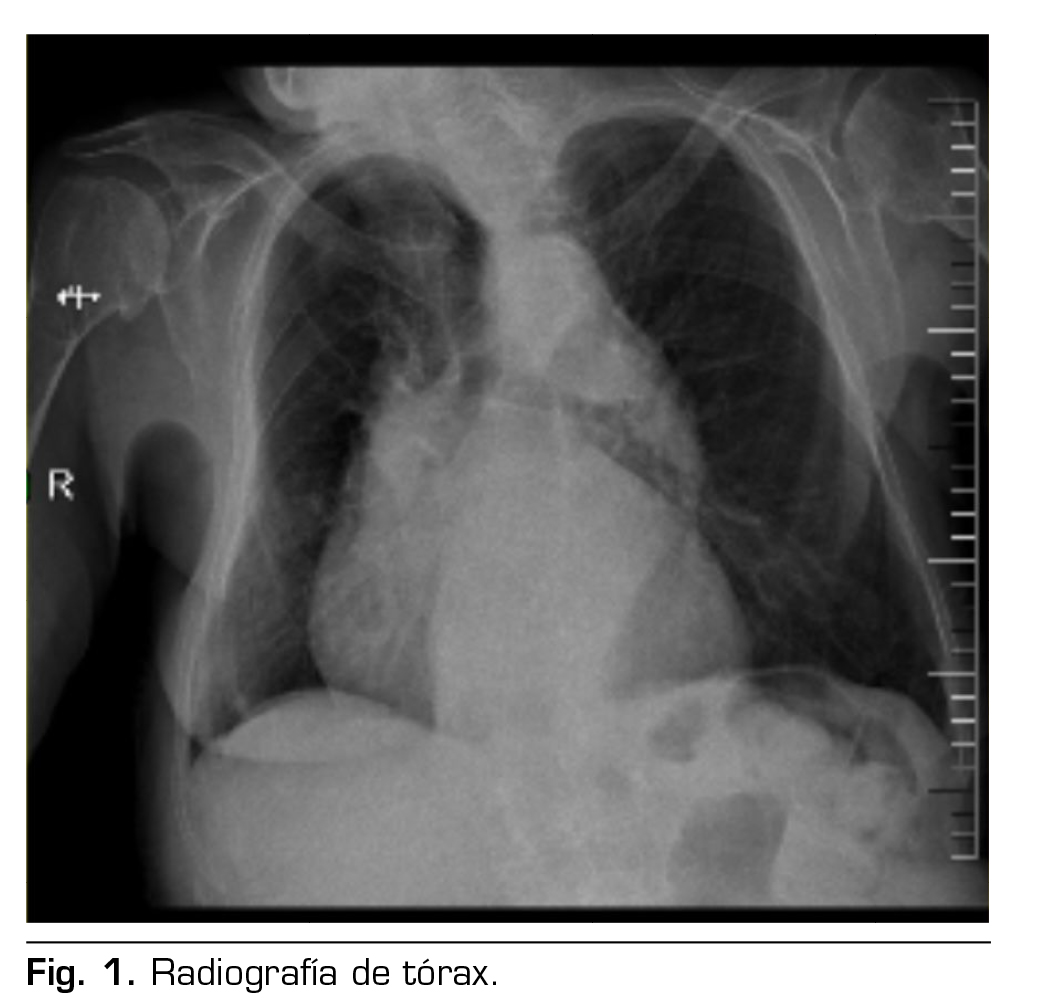

Presentamos el caso de una paciente de 88 años con diagnóstico de hernia inguinal izquierda que fue programada para hernioplastia electiva por cirugía ambulatoria en un hospital de día. En el estudio preanestésico se recoge que tiene antecedentes médicos de: hipertensión arterial controlada, fibrilación auricular en tratamiento con apixabán e insuficiencia cardiaca crónica compensada NYHA II, enfermedad pulmonar obstructiva con uso de oxígeno domiciliario nocturno, y no tiene antecedentes tromboembólicos; como antecedentes quirúrgicos: corrección de hernia discal a nivel de L5-S1 hace aproximadamente 20 años. Otros antecedentes de interés son los siguientes: cifoescoliosis moderada–severa, en imágenes diagnósticas como la radiografía de tórax anteroposterior, se observa cifoescoliosis severa y desplazamiento de mediastino a predominio derecho, como se muestra en la Figura 1; tiene un control ecocardiográfico que concluye función sistólica conservada, hipertrofia de ventrículo izquierdo, insuficiencia-estenosis aórtica severa, insuficiencia mitral moderada, insuficiencia tricuspídea severa, hipertensión pulmonar severa y dilatación moderada de aurícula izquierda. En el examen físico se confirma la cifoescoliosis dorsolumbar moderada-severa; en la evaluación de la vía aérea, se observa que tiene Mallampati 1, sin criterios de vía aérea difícil; analítica preoperatoria sin alteraciones de interés, paciente ASA III.